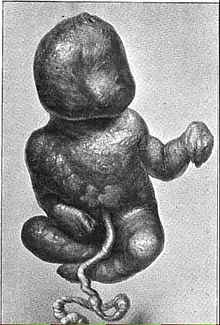

In 1880, German physician Friedrich Küchenmeister reviewed 47 cases of lithopedia from the medical literature and distinguished three subgroups: Lithokelyphos ("Stone Sheath"), where calcification occurs on the placental membrane and not the fetus; Lithotecnon ("Stone Child") or "true" lithopedion, where the fetus itself is calcified after entering the abdominal cavity, following the rupture of the placental and ovarian membranes; and Lithokelyphopedion ("Stone Sheath [and] Child"), where both fetus and sac are calcified. Lithopedia can originate both as tubal and ovarian pregnancies, although tubal pregnancy cases are more common.[2]

Originally from the Gascon village of Viulas near Lombez, Mathieu gave birth to ten children but only three survived infancy. At 37, she became pregnant, carried to full term and broke her water for the eleventh time, but never gave birth despite the efforts of a physician. She suffered from acute abdominal pain for two months, vaginal bleeding for five months, and felt discomfort for the rest of her life. This only eased when she laid on her back, making her bedridden and she experienced periodic paroxysmal attacks. Her case became notorious and her symptoms were popularly attributed to a spell cast by a sorceress whom Mathieu had rejected as a midwife. She consented to a public, three-day long necropsy after her death, which was attended by four doctors, three surgeons and their assistants. They found the calcified umbilical cord, placenta and a fully formed baby boy inside that weighed 3,916 grams (8 lb 10 oz). The lithopedion was found floating in white, odorless pus, which made it semi-mobile and would explain Mathieu's claim that she could still feel the baby moving inside her. The lithopedion was extensively described and pictured in a published memoir by François Bayle, one of the doctors present.[7] |